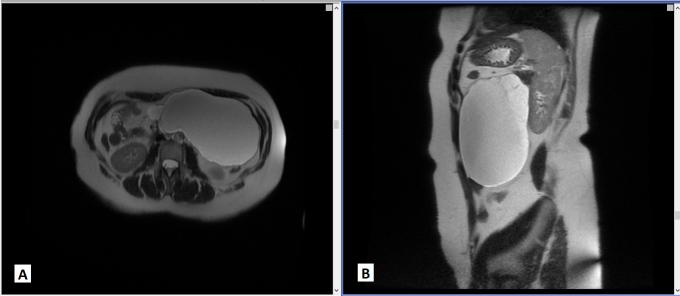

Cystic mesotheliomas (also called mesothelial inclusion cysts) are rare benign neoplasms that occur more often in young women. Symptoms are usually non-specific, demanding a thorough work-up. We report a case of a 40-year-old female patient with 2 prior caesarean sections presenting with a 3-month history of abdominal pain. Laboratory tests revealed microcytic hypochromic anaemia and an elevated tumour marker CA-125. An investigation identified a large cystic abdominal mass, mostly in the left side of the abdomen. A laparotomy was performed with total resection of the lesion. Histological assessment resulted in a diagnosis of a mesothelial inclusion cyst. The patient had no recurrence after 3 years.

Peritoneal mesotheliomas are rare conditions, and with benign features are even rarer.Mesothelial inclusion cysts, also known as benign cystic mesothelioma, occur more often in young to middle-aged women with excellent prognosis, although there are high rates of local recurrence.Investigation unmasks large abdominal lesions. A timely diagnosis is of the utmost importance, to prevent a dramatic change in outcome if severe complications develop.